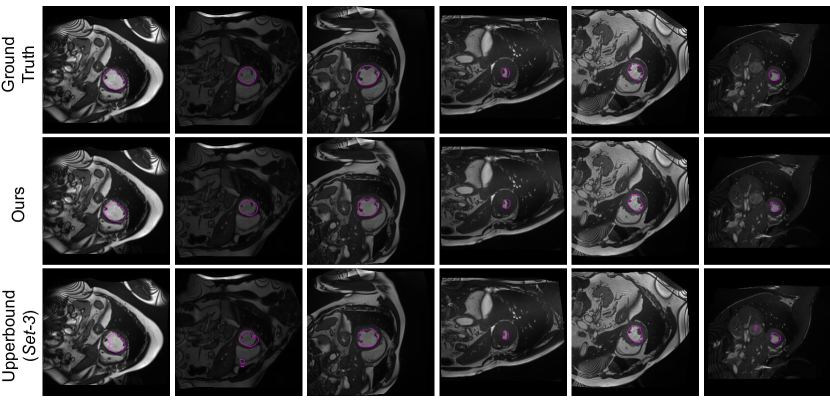

Figure 8: Qualitative results for the analyzed models under two different settings.

In addition to the numerical results presented before, we also depict qualitative results in Fig. 8 and Fig. 9. Particularly, Fig. 8 depicts the segmentation results for the models evaluated in Table 1. We see that results obtained by models with a single network typically under-segment the object of interest (first row) or generate many false positives (second row). Decoupling the decoding branches might reduce the false positive rate, however, it also tends to under-segment the target. Finally, we observe that both of our formulations achieve qualitatively better segmentation results, with the KL+Ent model yielding segmentations similar to those generated by the upper bound model. Furthermore, in Fig. 9, we illustrate additional qualitative results of our models. We observe that without the entropy term our model produces less confident predictions, which results in more noisy segmentations.

Qualitative evaluation is visually assessed in Fig. 10, which depicts the segmentation results across models on the Set-3 and Set-5 settings. Similarly to the visual examples in Fig. 8, single models generate inconsistent segmentations, which result in both large under and over-segmentations. Even though decoupling single models in dual-stream architectures seem to reduce the amount of false positives, it typically comes at the price of failing to identify target regions. In contrast, both of our models provide a substantial improvement on the segmentation quality, with the model integrating the KL and the entropy terms providing the closest results to the ground-truth.